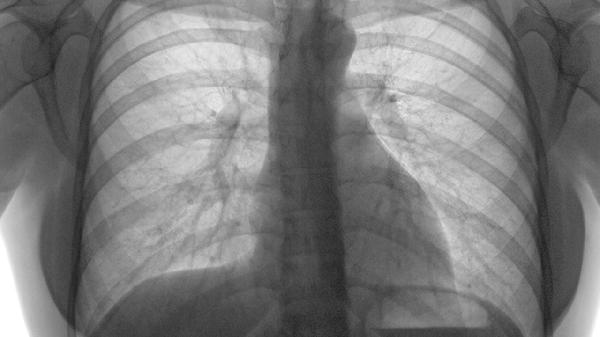

肺栓塞是肺动脉或其分支被血栓阻塞导致的急症,严重程度从轻度呼吸困难到猝死不等,主要包括肺梗死、循环衰竭、慢性血栓...